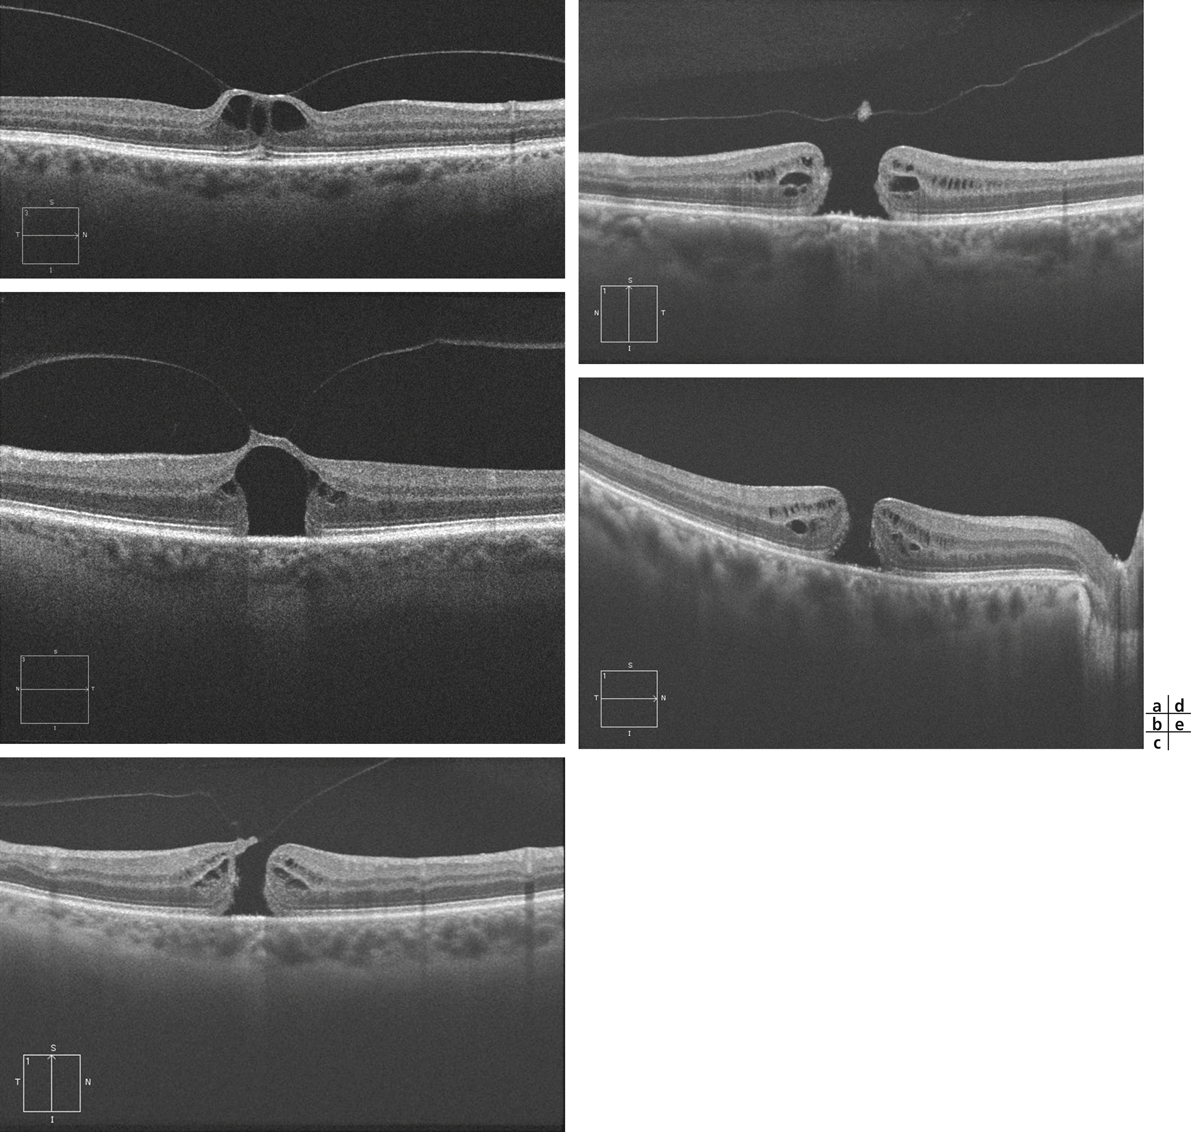

Fig. 13-14 Classification OCT des trous maculaires en stades.

Au stade I de trou maculaire (a, b), il n’y a pas encore de trou maculaire de pleine épaisseur constitué mais une « menace de trou maculaire » par traction vitréomaculaire. Selon l’importance de cette traction à l’OCT, le stade I est divisé en stades IA et IB. a. Au stade IA, la hyaloïde postérieure reste attachée à la région maculaire où elle prend un aspect hyper-réflectif. La fovéa en regard est surélevée et microkystique, le kyste fovéolaire reste limité à la rétine interne, la rétine externe est intacte ou de simples micro-altérations des segments externes peuvent être présentes. b. Au stade IB, le toit du kyste maculaire en regard de la traction est toujours présent, mais le kyste est associé à une ouverture franche des couches externes de la rétine. Les stades II, III et IV correspondent à des trous maculaires de pleine épaisseur. c. Au stade II, le toit du kyste est rompu, avec une adhérence toujours présente de la hyaloïde postérieure sur le bord du trou. Les bords du trou maculaire sont épaissis avec des kystes hyporéflectifs. d. Au stade III, la hyaloïde postérieure est détachée des bords du trou maculaire réalisant un aspect d’opercule. Le vitré n’est pas encore détaché de la papille. e. Au stade IV, la hyaloïde postérieure est complètement détachée de la région maculaire et du nerf optique.

Dans la classification de Gaudric, au stade I de trou maculaire, il n’y a pas encore de trou maculaire de pleine épaisseur constitué, mais une « menace de trou maculaire » par traction vitréomaculaire. Selon l’importance de cette traction à l’OCT, le stade I est divisé en stade IA et IB. Au stade IA, la hyaloïde postérieure reste attachée à la région maculaire où elle prend un aspect hyper-réflectif. La fovéa en regard est surélevée et microkystique ; le kyste fovéolaire reste limité à la rétine interne et la rétine externe est intacte ou de simples micro-altérations des segments externes peuvent être présentes. Au stade IB, le toit du kyste maculaire en regard de la traction est toujours présent, mais le kyste est associé à une ouverture franche des couches externes de la rétine et l’acuité visuelle chute (fig. 13-14).

Les stades II, III et IV correspondent à des trous maculaires de pleine épaisseur. Au stade II, la coupe OCT montre la rupture du toit du kyste, avec une adhérence toujours présente de la hyaloïde postérieure sur le bord du trou. Les bords du trou maculaire sont épaissis avec des kystes hyporéflectifs (fig. 13-14).

Au stade III, la hyaloïde postérieure est détachée des bords du trou maculaire réalisant un aspect d’opercule. Le vitré n’est pas encore détaché de la papille (fig. 13-14). Enfin, au stade IV, la hyaloïde postérieure est complètement détachée de la région maculaire et du nerf optique (fig. 13-14). Au fond d’œil, l’anneau de Weiss peut être visible.